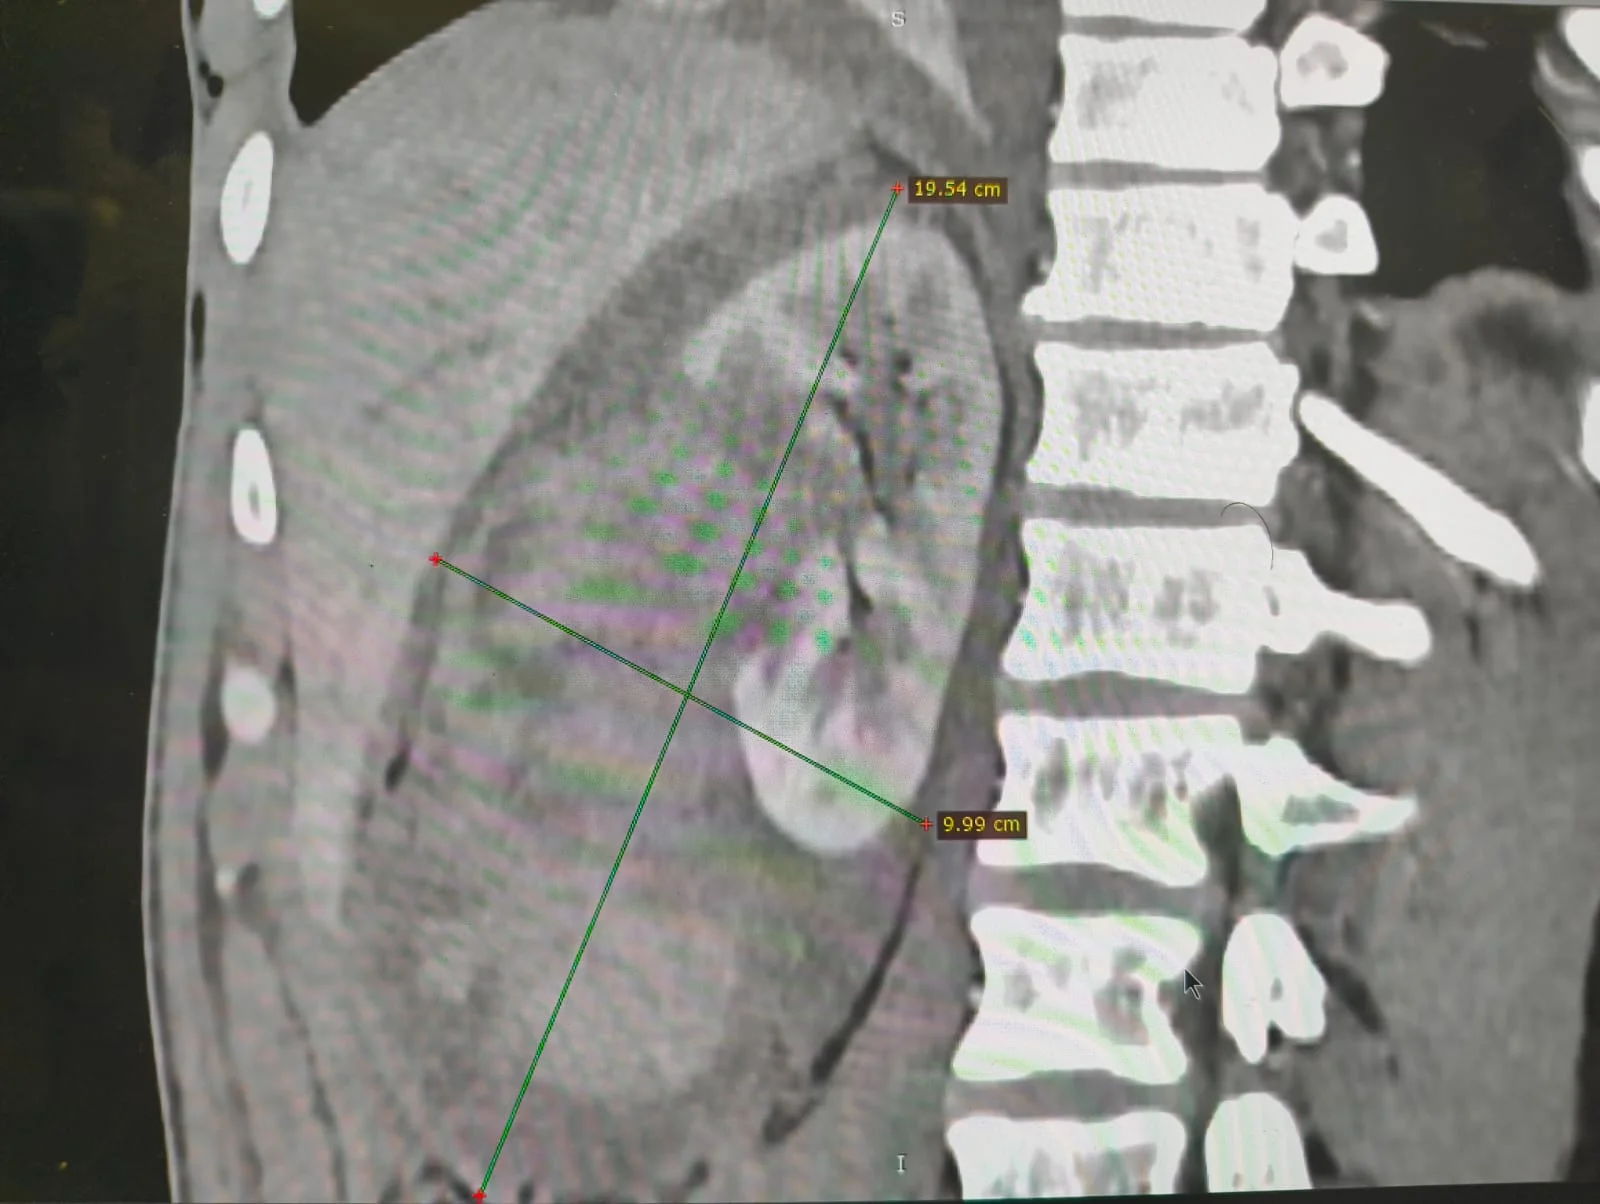

استمرارًا لمسيرة النجاح التى يحققها مستشفى كفر الشيخ الجامعى فى تقديم خدمات طبية متقدمة، نجح الفريق الطبى بوحدة الأشعة التداخلية تحت إشراف الدكتور محمود غلابمدير وحدة الأشعة التداخلية و استشارى الأشعة التداخلية، و زميل الأشعة التداخلية بجامعة هيروشيما، و مدرس الأشعة التداخلية بجامعة كفر الشيخ – فى إنقاذ حياة شاب تعرّض لحادث أدى إلى قطع جزئى فى الشريان الكلوى الأيمن مصحوبًا بتجمع دموى، و ذلك دون اللجوء إلى استئصال الكُلى.

تمكّن فريق الأشعة التداخلية بجامعة كفر الشيخ بقيادة د. محمود غلاب من إجراء تدخل طارئ ناجح تم خلاله سدّ التمدد الشريانى مع الحفاظ الكامل على التغذية الدموية لباقى أنسجة الكُلى، و هو ما يُعد من أبرز و أهم مميزات الأشعة التداخلية التى تهدف إلى إنقاذ العضو المصاب دون جراحة مفتوحة، و بأعلى درجات الدقة مع تقليل المضاعفات و فترة التعافى.

تم إجراء هذا التدخل فجر يوم الاثنين بعد ساعات قليلة من الإبلاغ عن حالة المريض المحجوز بالمستشفى العام، حيث جرى تنسيق عاجل مع إدارة مستشفى كفر الشيخ الجامعى لتوفير جميع المستلزمات الطبية اللازمة، و تم نقل المريض على الفور إلى المستشفى الجامعى لإجراء التدخل و إنقاذ حالته فى توقيت حرج.